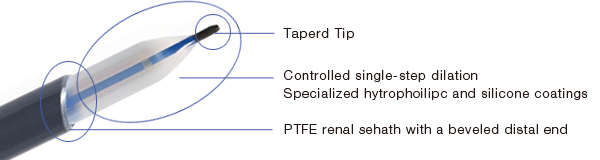

Designed for smooth, atraumatic insertion into the patient's anatomy, features such as the fully radiopaque tip and advanced hydtrophilic and silicone coatings on the balloon ensure precise visualization and smooth, controlled percutaneous and ureteroscopic access.

Controlled single−step dilation of the balloon facilitates accurate and predictable access thus improving efficiency and safety of procedures.

EZDilate Balloon Dilators are tapered at the distal end for smooth, atraumatic insertion into the patient anatomy.

- The Nephroscoptymy balloon dilators each include a PTFE renal sheath with a taperd distal edge which ensures easy placement over the balloon even in challenging surrounding tissue

- Hydrophilic and silicone coatings on EZDilate balloons promote smooth, low-friction positioning.